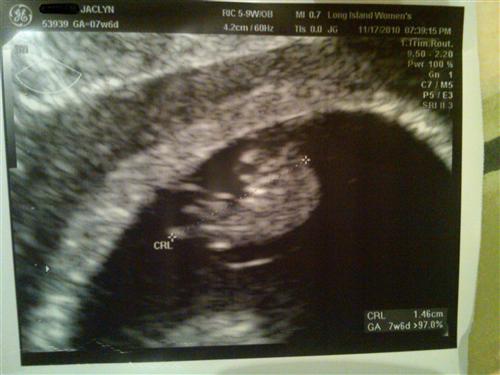

8 week sono